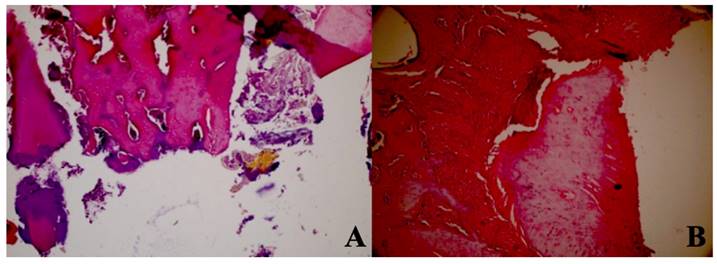

After micro CT analysis, the mandibles of the rats were separated and fixed in 10% formalin solution (Fisher Scientific, Hampton, USA). Samples were decalcified in formic acid buffered with citrate for 48 hours and then embedded in paraffin. 5 µm-thick serial sections were taken from the region around the extraction socket in the longitudinal plane and stained with hematoxylin and eosin (HE) for histopathological examination. For each sample, three sections were examined for new bone formation, dead bone areas (without viable osteocytes), inflammatory cell infiltration, and epithelial cell regeneration under a light microscope at ×100 magnification (Olympus, Tokyo, Japan). The examination process was carried out by an experienced pathologist who was unaware of the study protocol.

A statistically significant difference was observed between new bone formation, dead bone areas, epithelial cell regeneration, and inflammation cell rates of sham, control, 405 nm, 445 nm, 660 nm, and 808 nm groups (p=0.0001). The sham group's mean new bone formation rate was statistically significantly lower than the mean rates of the other groups except the control group(p=0.0001). In addition, the control group's rate was statistically significantly lower than the mean rates of the 405 nm, 445 nm, 660 nm, and 808 nm groups (p=0.001, p=0.0001). No statistically significant difference was observed between the other groups (p>0.05) (Figure 9,10).

New bone formation. A In the SHAM group, there is a live bone in the form of bands in the defect area, on and around the tooth germ, areas of new bone formation in the environment, and dead bone areas in the near-surface areas. H&E, X40. B In the control group, there are dead bone fragments on the surface, live bone on both sides, and new bone formation areas around the granulation tissue in the middle section of the defect area. H&E, X40. C In the laser 405 nm, live bone in the defect area, lower margin, granulation tissue, and dead bone fragments at the left end and new bone formation in large areas are observed. H&E, X40. D In the laser 445 nm, dead bone, live bone, and new bone formation areas are observed in the defect area around the tooth, and a small amount of granulation tissue is observed. H&E; X40. E In the laser 660 nm, intense new bone formation is observed around the tooth, between the living bone areas. H&E; X40. F In the laser 808 nm, dense new bone formation and granulation tissue are seen between living bones. H&E; X40.

Regarding the number of dead bones, the mean value of the 445 nm groups was statistically significantly higher than the mean values of the other groups except the control group (p=0.007, p=0.001). The control group's mean value was statistically significantly higher than the other groups, except for the 445 nm group (p=0.021, p=0.001). The rates of the 405 nm and 880 nm groups were significantly higher than the sham and 660 nm groups (p=0.002, p=0.001) (p=0,020, p=0,007). Additionally, while no statistically significant difference was observed between the other groups (p>0.05) (Figure 11,12).

Regarding the epithelial cell regeneration, the mean values in the 880 nm and 660 nm groups were significantly higher than in the sham, control, 405 nm, and 445 nm groups (p=0,001). No statistically significant difference was observed between the other groups (p>0.05) (Figure 13,14).

Dead bone count. A In the control group, granulation tissue, and minimal new bone formation were seen between large areas of dead bone. H&E; X40. B In the Laser 660 nm group, inflammation, and granulation tissue were observed around the dead bone fragments. H&E; x100.

Epithelial cell regeneration. A In the control group, epithelial regeneration was observed on the wound surface. H&E; X40. B In the Laser 660 nm group, epithelial regeneration was observed on the wound surface. H&E; X40. C In the Laser 808 nm group, epithelial regeneration was observed that covers the defect area and surrounds the deep dead bone. H&E; X40.

Inflammation Cell Count. A In the SHAM group, areas of inflammation were observed around dead bone fragments. H&E; x100. B In the 445 nm group, intense inflammation, and granulation tissue formation were observed around the new bone formation. H&E; x100.